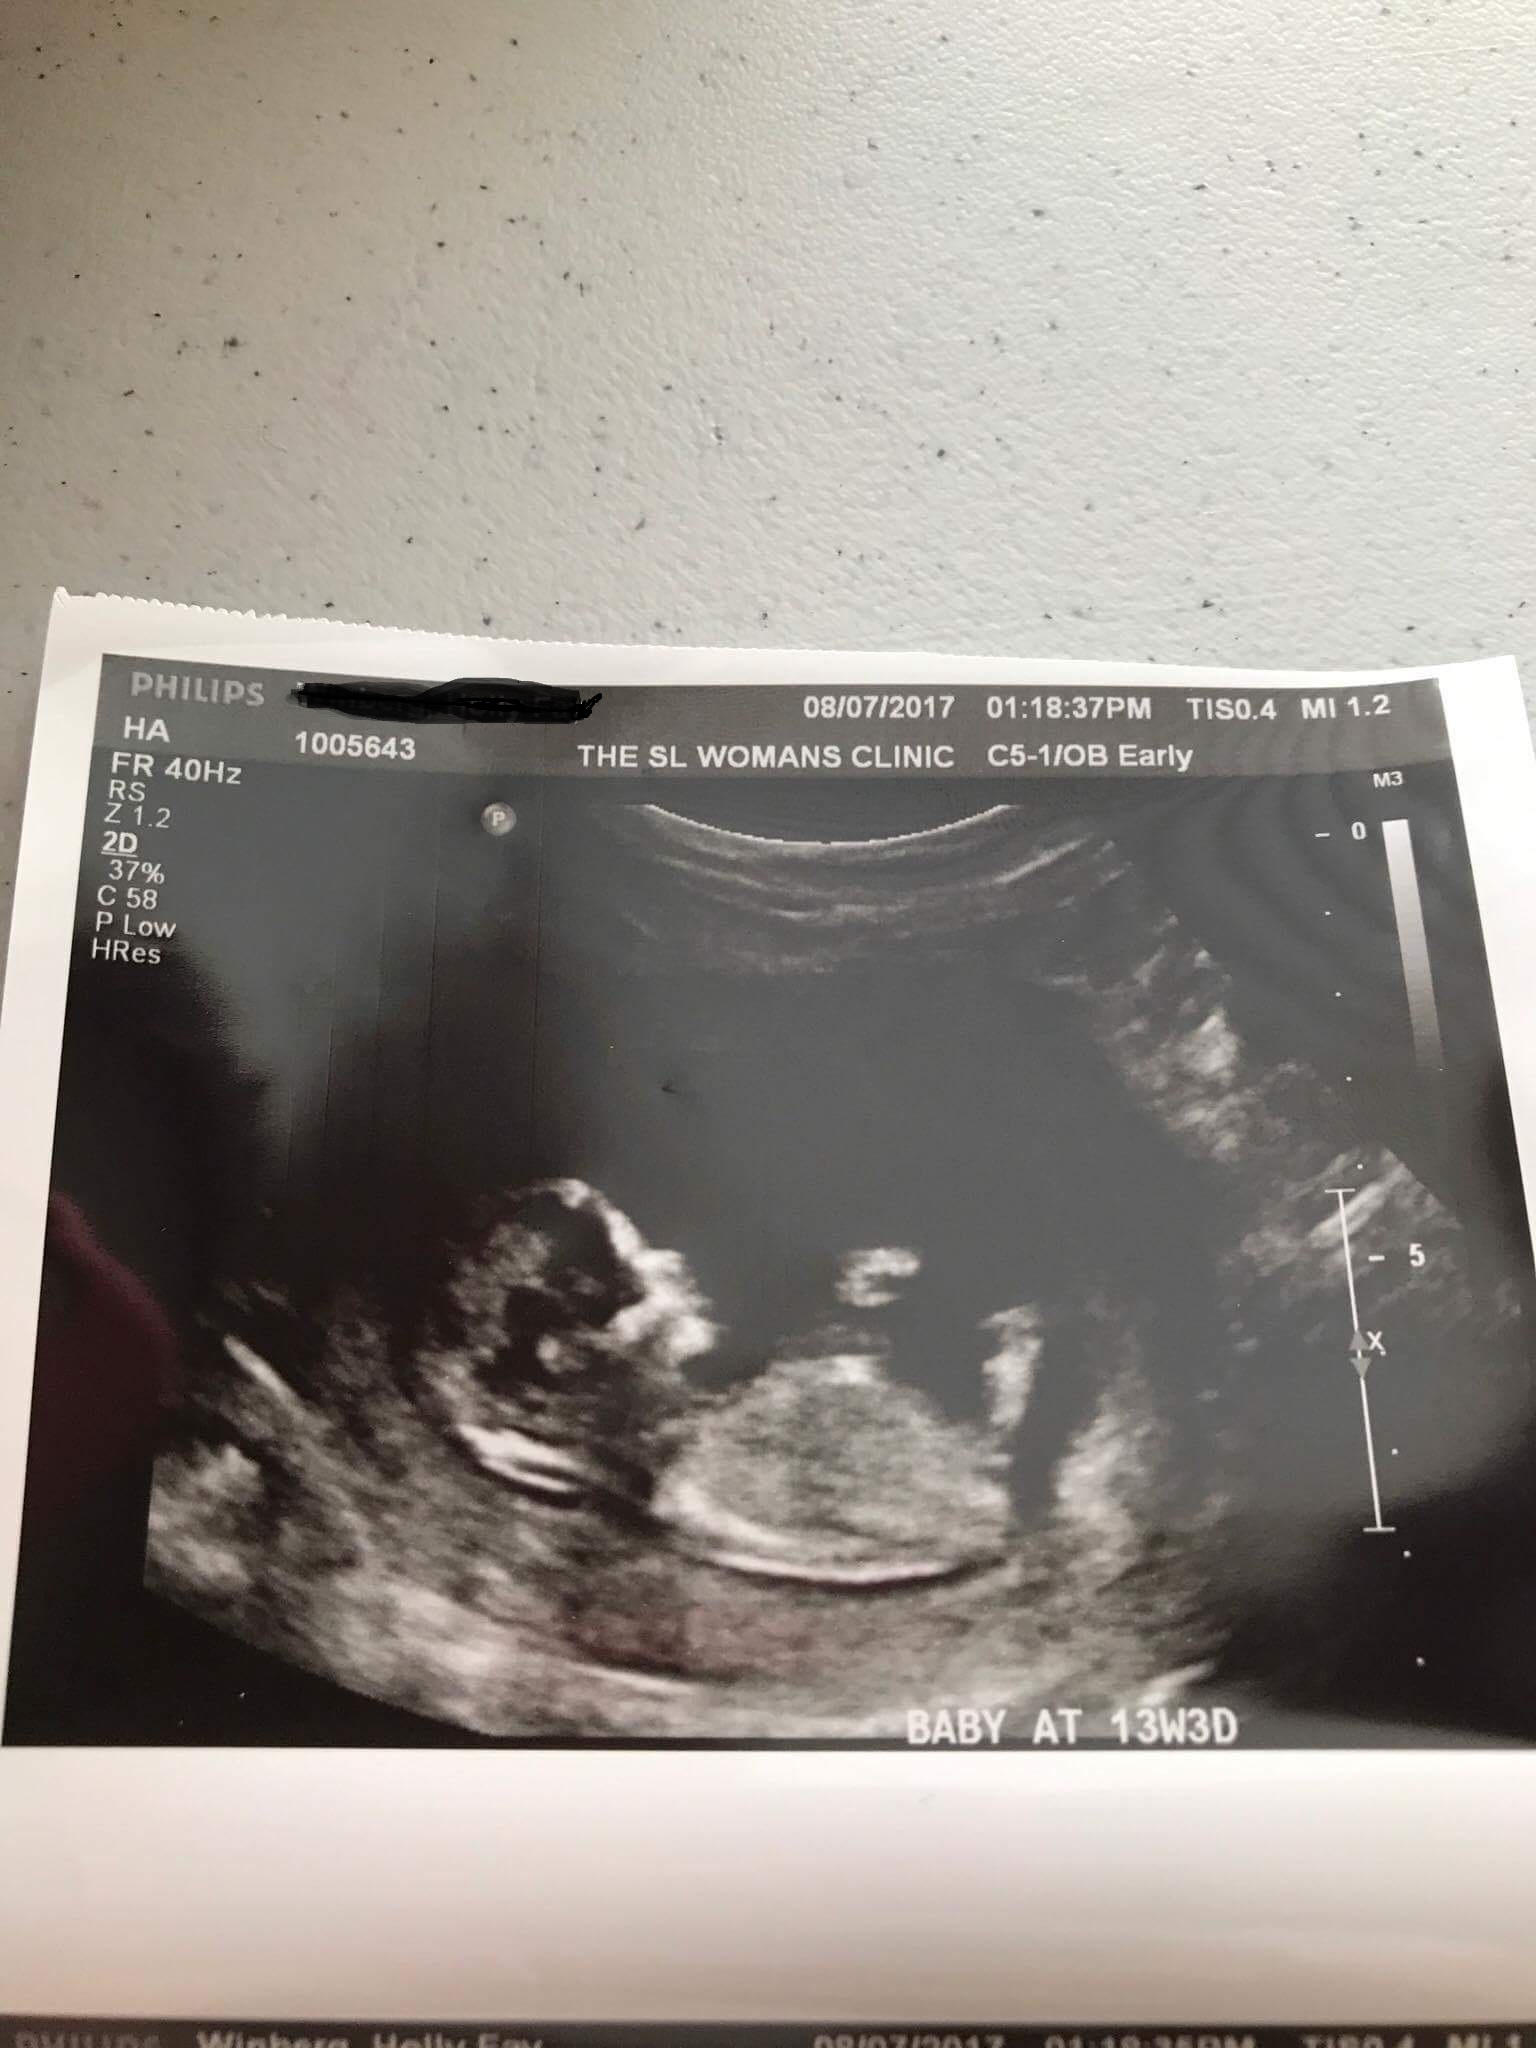

Could you please let me know what you think for a nub on this one for by BFF!!!

I'm getting a boy vibe

That is all she has. I was getting a boy vibe too :)

Boy vibe but skull looks kind of girly.

I think it's a boy, and to me, skull is boyish too. It's the chin LOL (the chin was the ONLY thing different between my daughter and sons' ultrasounds)